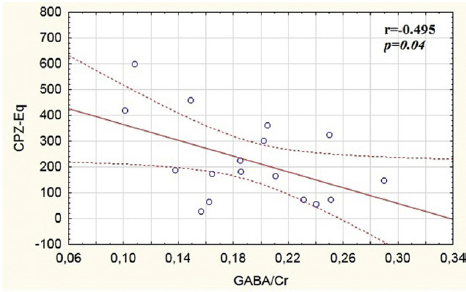

Fig. 3 Association between GABA/Cr and treatment.

The main effects on the GABA/Cr (t[45] = 4.17, P < 0.01) (Fig. 2A) and GABA/GLX (t[45] = 2.84, P < 0.01) (Fig. 2B), were found in the left ACC (t[45] = 4.17, P < 0.01), with the patients having lower GABA/Cr and GABA/GLX ratios as compared to the control group. Also significant negative correlation (r = −0.49, P = 0.04) between GABA/Cr in the right ACC and the current daily dosage of antipsychotic medication in CPZ-Eq was found (Fig. 3).

This study reveals for the first time a significant reduction of (GABA) (25%) and GABA/GLX ratio (20%) in left AC of UHR subjects. According to (de la Fuente-Sandoval, Int J Neuropsychopharmacol 2015;19[3]) and association of (GABA) with daily dosage of medication found, this reduction may be caused by the antipsichotic treatment.

Fig. 3 Association between GABA/Cr and treatment.

Fig. 3 Association between GABA/Cr and treatment.